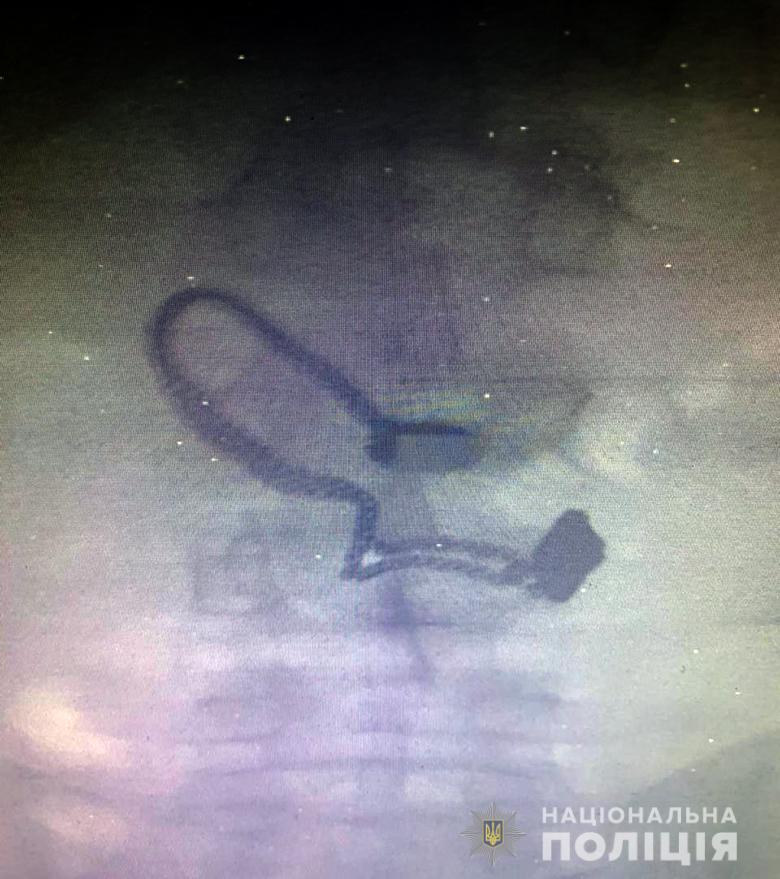

Грабителем оказался 26-летний житель Луганской области, ранее уже судимый за кражи. Его задержали. Во время поверхностного осмотра у мужчины нашли кошелек потерпевшей. Позже он признался полицейским, что сорванную цепочку проглотил.

"Во время медосмотра на рентген-снимке задержанного врачи обнаружили украшение", - сообщают в полиции.